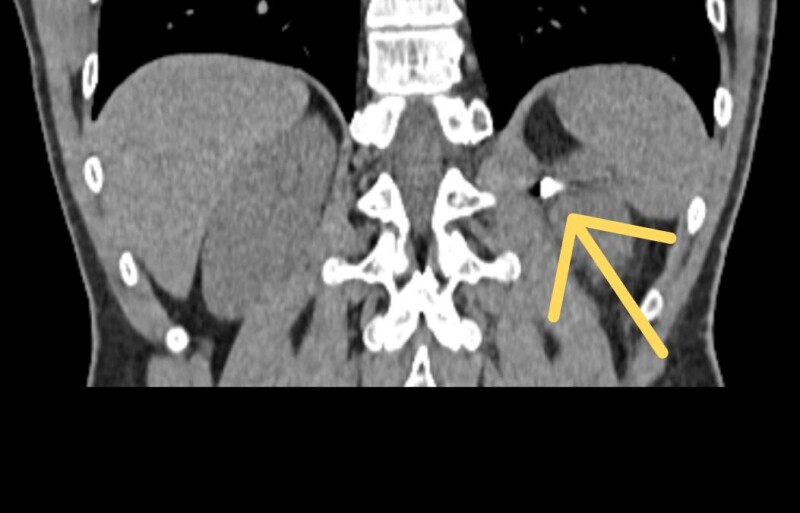

Пацієнт-військовий із наслідками мінно-вибухової травми звернувся до медиків через постійний ниючий біль у зоні лівої нирки. Обстеження показало уламкове пошкодження периренального простору лівої нирки – уламок розміром 10х10 мм залишався в організмі після попереднього лікування в іншому медичному закладі. Його складне розташування біля магістральних судин ускладнювало хірургічне лікування.